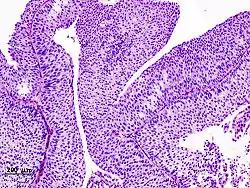

![]() التشريح المرضي النسيجي لسرطانة الخلايا الانتقالية في المثانة بخزعة عبر الإحليل وتلوين بالهيماتوكسيلين إيوسين. التشريح المرضي النسيجي لسرطانة الخلايا الانتقالية في المثانة بخزعة عبر الإحليل وتلوين بالهيماتوكسيلين إيوسين. | |

معظم حالات سرطان المثانة هي ظهارية المنشأ، وتشكل سرطانة الخلايا الانتقالية 90% منها والباقي يشكلها كل من السرطانة الغدية والسرطانة حرشفية الخلايا.[41][42] من الأنواع النادرة الأخرى السرطانة صغيرة الخلايا واللمفوما والغرن.